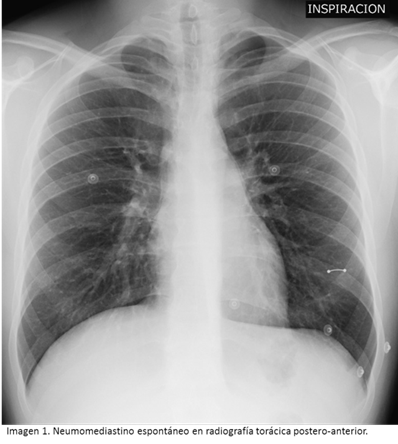

El diagnóstico de sospecha de NE se obtuvo con radiografías postero-anteriores (PA) de tórax, excepto en dos pacientes con marcado enfisema subcutáneo. No obstante, en catorce pacientes se completó el estudio con tomografía computarizada (TC) torácica (con contraste intravenoso). En estas pruebas de imagen no se observó ningún neumotórax concomitante, pero si presencia de derrame pleural hasta en cuatro ocasiones. Las imágenes radiológicas características de NE se muestran en las imágenes 1 y 2. Tras el diagnóstico, se añadieron algunas exploraciones complementarias para estrechar el diagnóstico diferencial, como esofagograma o laringoscopia, que excluyeron posibles complicaciones secundarias como la perforación esofágica y/o del árbol traqueobronquial.

El diagnóstico de NE se ve a menudo entorpecido por el hecho de que, además de su infrecuencia, el dolor torácico y la disnea (sus síntomas más frecuentes), están presentes en multitud de patologías cardiopulmonares [4], [6]. Se confirma por radiografía de tórax PA, incluyendo región cervical. Sus signos radiológicos incluyen el signo del diafragma continuo (interposición de aire entre el pericardio y el diafragma, que se vuelve visible en el mediastino central) y en algunos neonatos puede observarse el "Signo de Spinnaker" (desviación supero-externa de lóbulos tímicos) cuando el aire asciende el timo por encima del corazón y lo separa de la silueta cardíaca [3], [10], [18]. El NE es raro en niños, con un impacto bimodal que alcanza su punto máximo en niños menores de siete años de edad y luego nuevamente en la adolescencia. A pesar de que el diagnóstico se realiza mediante exploración física y radiografía de tórax, ya existen estudios que sugieren la importancia del método ecográfico en la detección infantil y neonatal de esta patología [19] [20].

Se concluye que el NE es una entidad benigna e infrecuente, típica de varones jóvenes que presentan disnea, dolor torácico y/o enfisema subcutáneo, sin existir causa primaria aparente. El diagnóstico se confirma por radiografía de tórax PA, aunque suele completarse el estudio con TC para descartar complicaciones de gravedad. Sus factores predisponentes más frecuentes son el asma, el tabaquismo y las drogas inhaladas entre otros. Así mismo, también puede desencadenarse por vómitos, tos, crisis asmática y otras maniobras de Valsalva. Suele cursar de forma autolimitada, resolviéndose de forma conservadora, aunque pueden existir recurrencias.